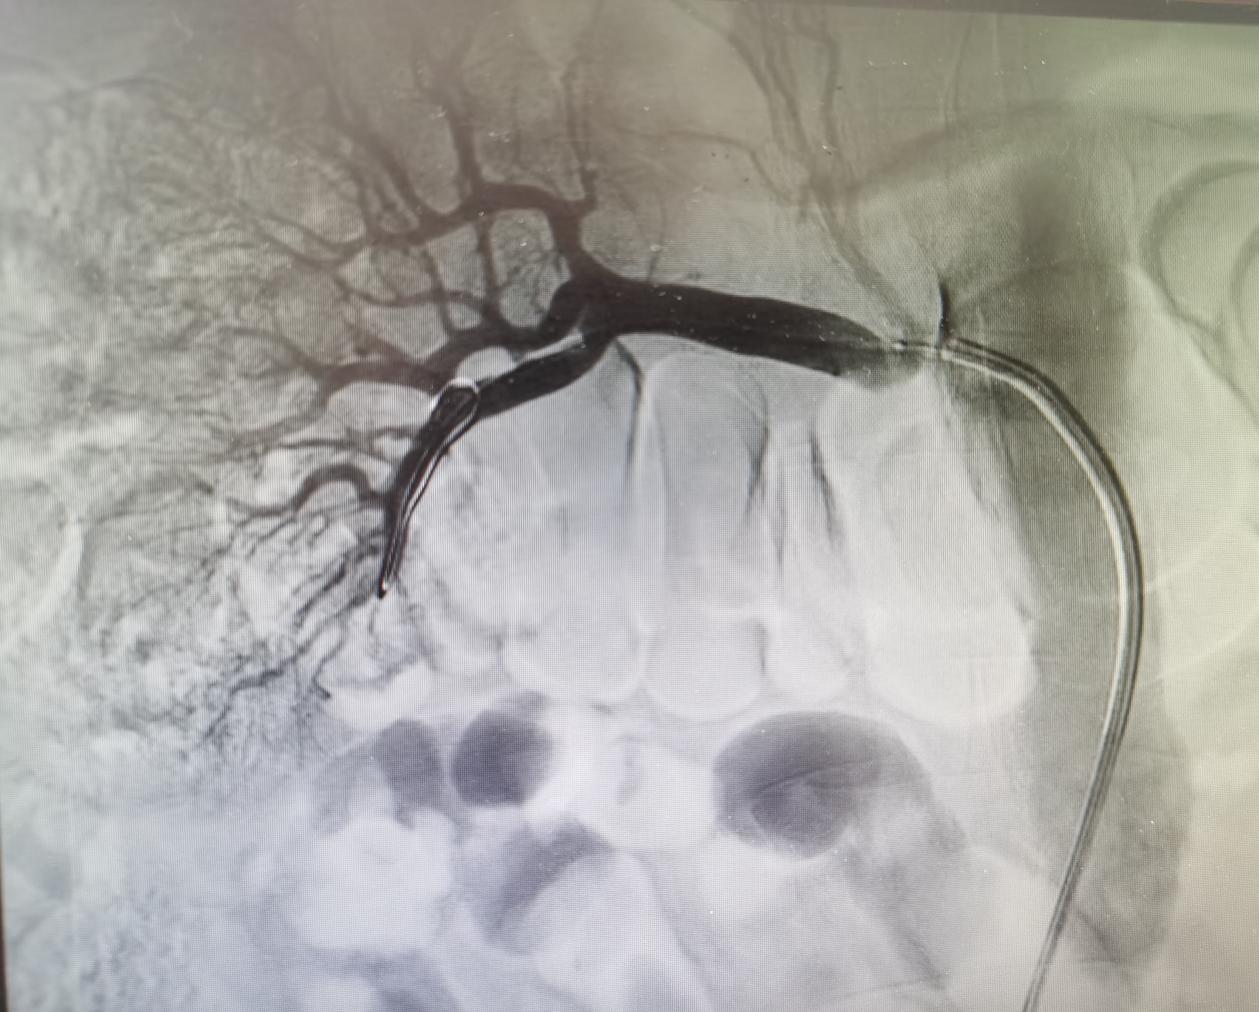

最终右肾恢复血供

“但他右肾动脉血管位置十分‘刁钻’,术中反复置入导丝脱出,柳海华主任利用‘热塑型’的技巧,最终顺利植入了支架。”袁东说,支架置入后,患者右侧肾脏供血明显改善,自术后起尿量明显增多,肾脏又恢复了往日的“活力”。“为了最大程度地减轻造影剂对肾功能的损伤,术后我们再次为患者进行了CRRT治疗,次日复查患者肾功较前明显好转,血肌酐下降至正常水平。”袁东说。